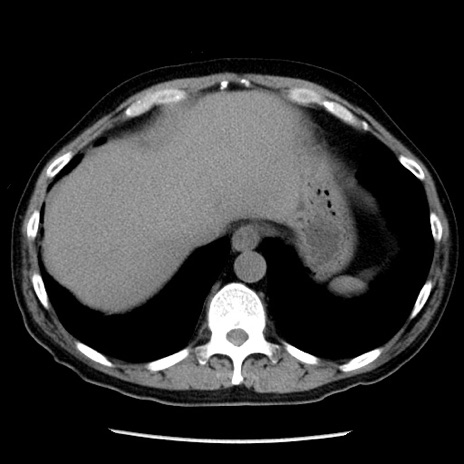

症例29(横断像)

【症例】40歳代男性

【現病歴】2日前から胃痛あり。徐々に周期的な激痛に変化した。本日になっても激痛があるため受診。

【身体所見】意識清明、BT 38-39℃台あり、腹部:膨満、やや硬、右下腹部に圧痛あり。

【データ】WBC 8500、CRP 23.26